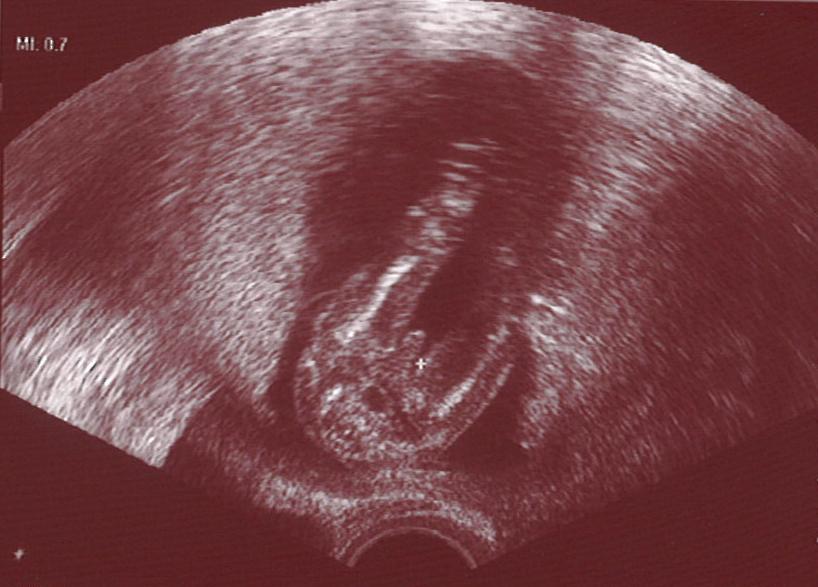

Kurz zu mir: seit heute wissen wir, dass es ein Junge wird! Yippeh! Wobei es mir ja wurst war, Hauptsache gesund... Aber ich hatte ein Jungengefühl. Kleines Bildchen im Anhang: ziemlich eindeutig. Man sieht die Beine und den Po, man schaut von unten drauf, und natürlich den Schniedel...

Baby 15+6 - 2 klein.JPG

Wahnsinn, wie genau man das in der 16. Woche (bist du doch, oder?) schon sehen kann! Hätte ich nicht gedacht! Auf jeden Fall herzlichen Glückwunsch! Jetzt könnt ihr ja anfangen Namensbücher zu wälzen! *rotfl*

Katz-Le: Wahnsinn, wie genau man alles auf so einem US-Foto sehen kann :ohnmacht: Glückwunsch zu eurem Buben!!